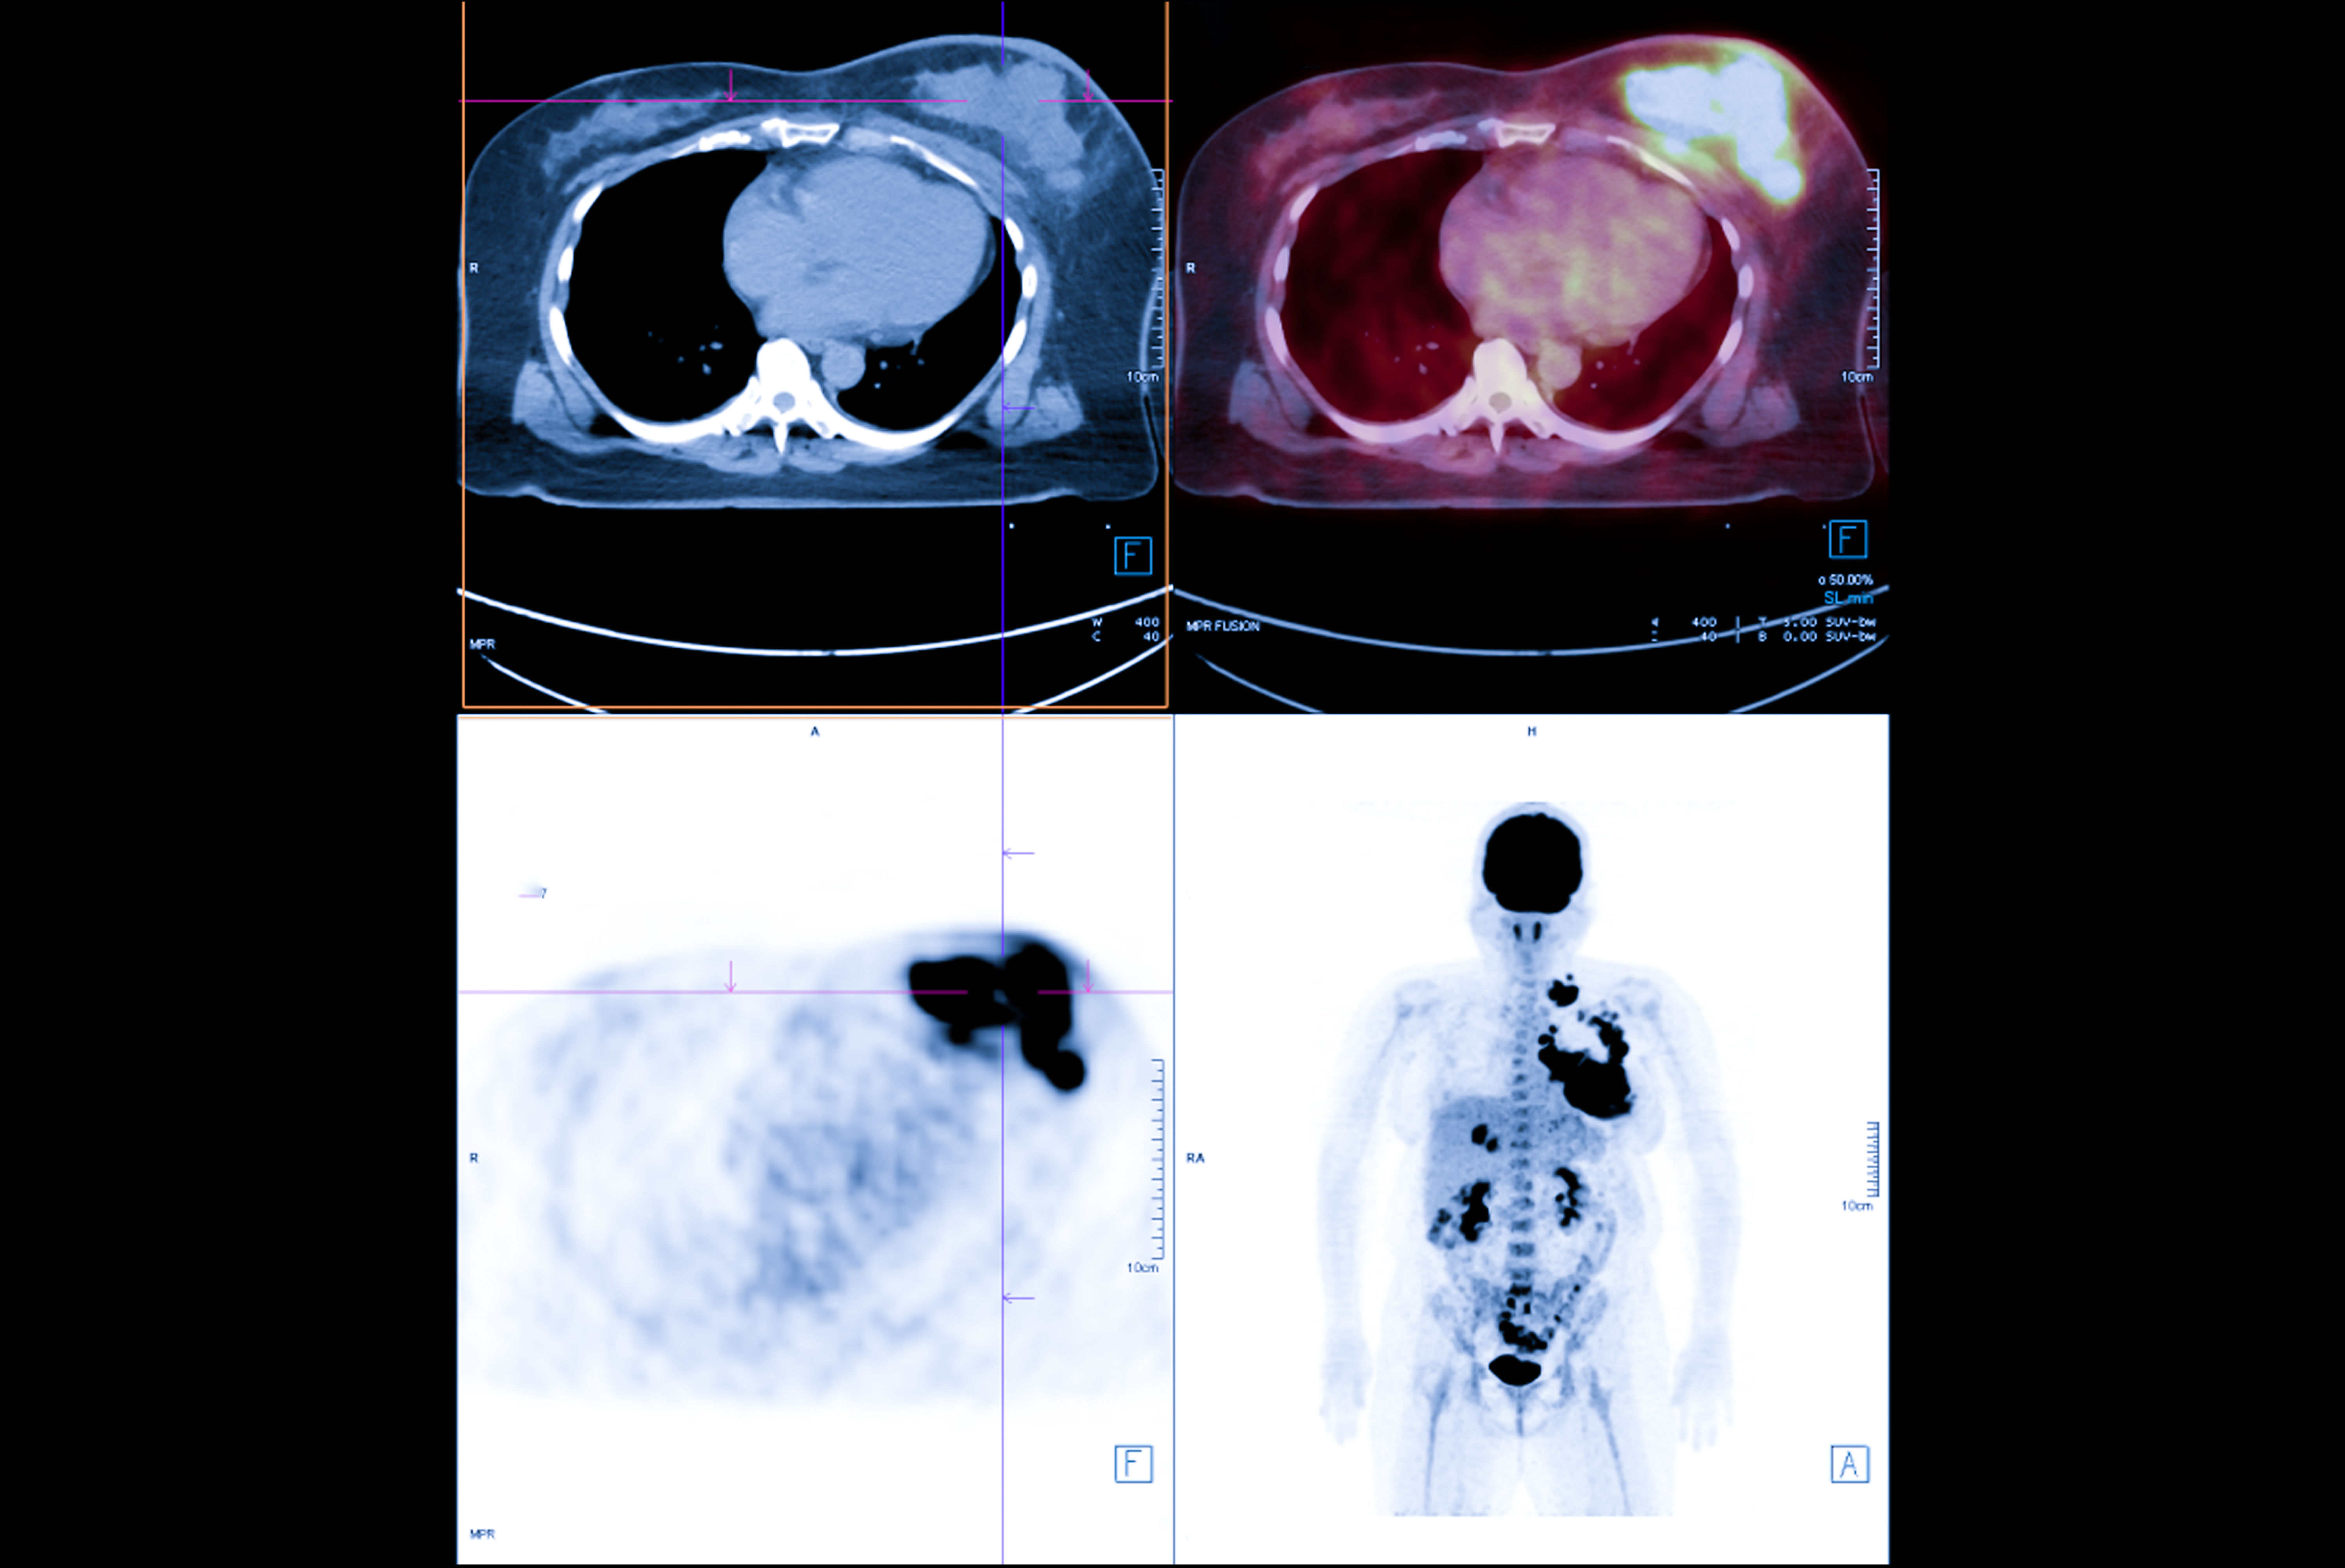

The updated version provides new CE-marked functionalities for displaying and analyzing nuclear medicine images across modalities, including PET/CT, SPECT/CT, PET/MR, and RTDOSE, the Stockholm-based firm said in a statement.

The new Hermia functionalities include computer-assisted organ segmentation, the Dmax tool for quantifying lesion spread in disseminated disease, and a split tool for manual separation of adjacent lesions or physiological uptake.